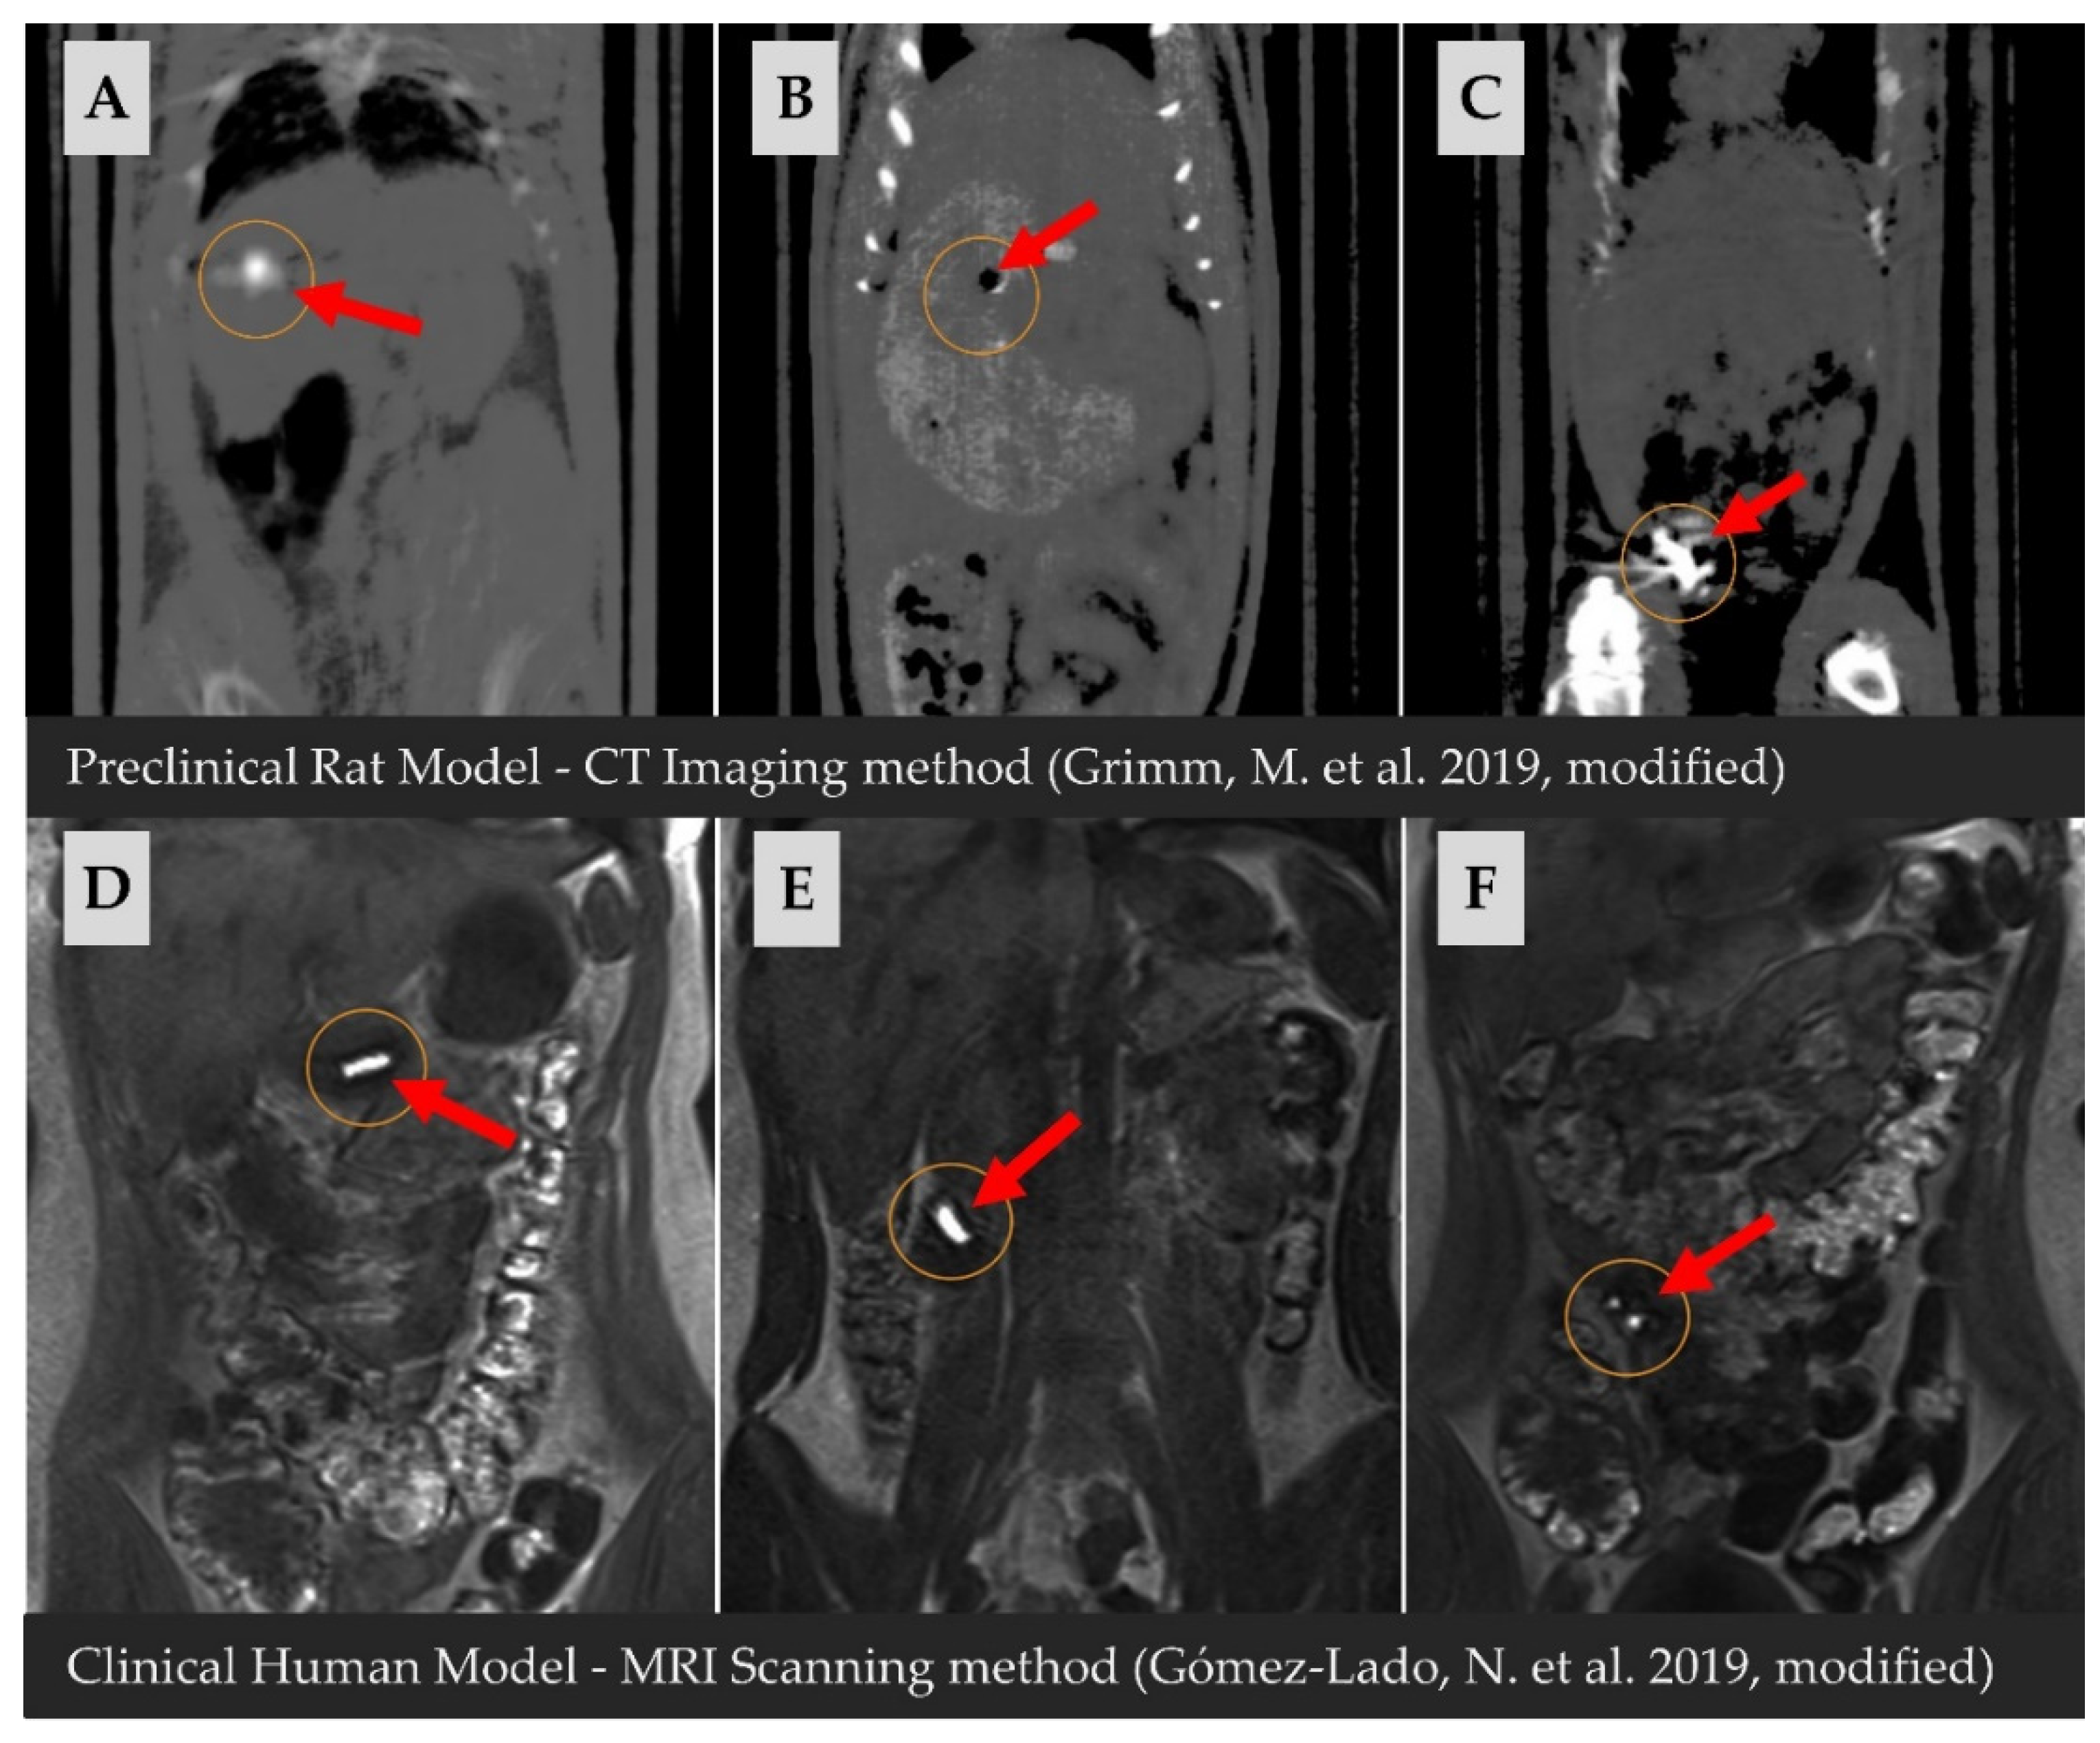

- Grimm, M.; Ball, K.; Scholz, E.; Schneider, F.; Sivert, A.; Benameur, H.; Kromrey, M.L.; Kühn, J.P.; Weitschies, W. Characterization of the Gastrointestinal Transit and Disintegration Behavior of Floating and Sinking Acid-Resistant Capsules Using a Novel MRI Labeling Technique. Eur. J. Pharm. Sci. 2019, 129, 163–172. [Google Scholar] [CrossRef]

- Gómez-Lado, N.; Seoane-Viaño, I.; Matiz, S.; Madla, C.M.; Yadav, V.; Aguiar, P.; Basit, A.W.; Goyanes, A. Gastrointestinal Tracking and Gastric Emptying of Coated Capsules in Rats with or without Sedation Using CT Imaging. Pharmaceutics 2020, 12, 81. [Google Scholar] [CrossRef]